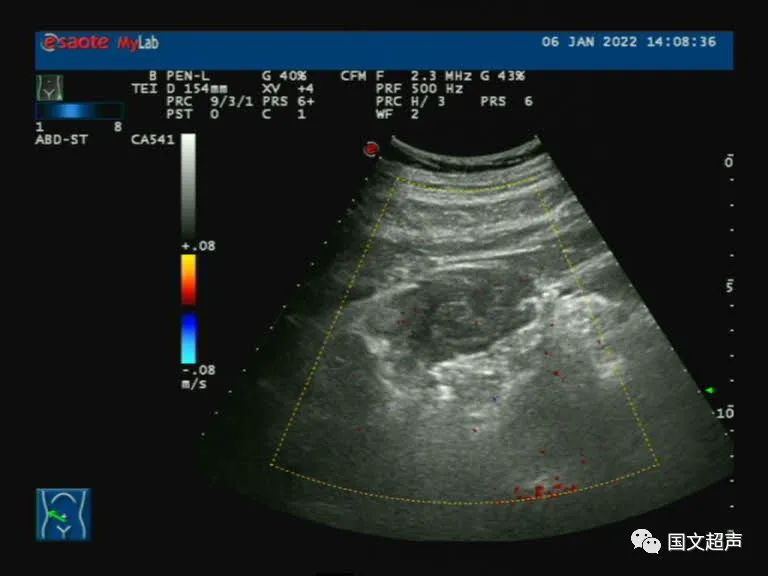

超聲檢查:肝右前葉下段探及混合回聲,形態(tài)尚規(guī)則,邊界較清晰,CDFI:血流信號不明顯。結(jié)合增強CT檢查結(jié)果,考慮肝膿腫,行抗感染及對癥治療。